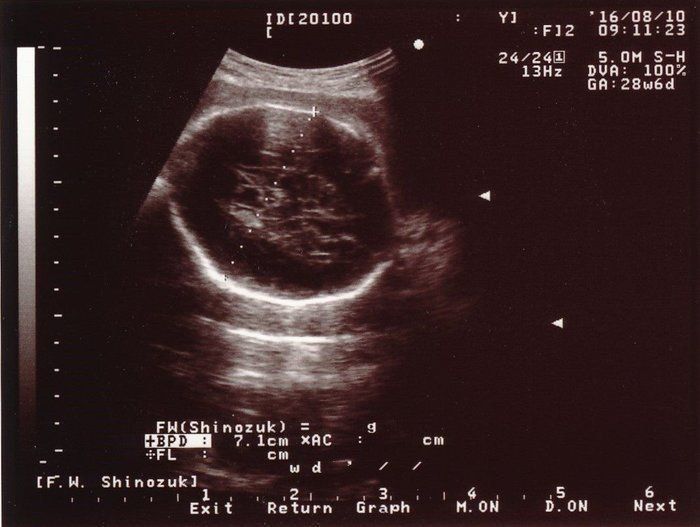

小吉さんの妊娠28週目のエコー写真

赤ちゃんの頭の大きさ(BPD)とお腹周り(AC)を測りました。赤ちゃんの成長は順調そのものでしたが、血液検査の結果で貧血の治療が必要となり、服薬はもちろんのこと、点滴のため週2回程度の病院通いが始まりました。

こちらは赤ちゃんのお尻の写真です。中央右寄り、お尻が上を向いていますので、頭が画面右下奥にあると思って見てください。女の子が確定した写真ですが、私の中では「やっぱり」という思いでした。